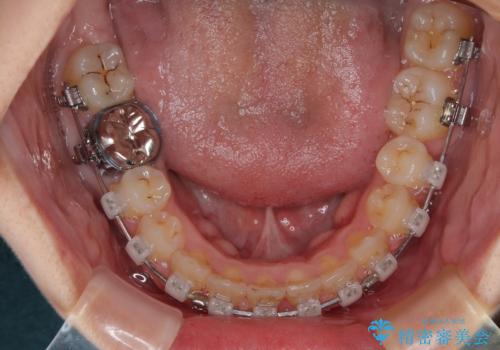

- クリアブラケット

マウスピース装着は煩わしいとのことで、表側のワイヤー装置にて矯正治療を行うこととしました。

前歯のクラウンは、歯肉内深くに削り込まれており、歯肉の炎症が継続していたため、矯正治療後に歯周外科処置を行い、歯肉の腫れを改善させました。